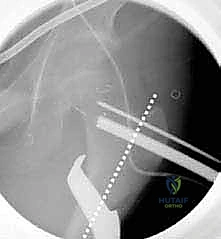

3. إدخال السلك الدليلي (Guide Wire)

تحت توجيه الأشعة السينية المباشرة داخل غرفة العمليات (C-arm)، يقوم الدكتور هطيف بإدخال سلك دليلي في عنق ورأس عظم الفخذ بالزاوية الصحيحة والمحسوبة بدقة.

4. القطع العظمي (The Osteotomy)

باستخدام منشار جراحي دقيق جداً وعالي السرعة، يتم إجراء قطع عرضي في عظم الفخذ في المنطقة المحددة. هذه الخطوة تفصل الجزء العلوي (الرأس والعنق) عن الجزء السفلي (جسم العظم).